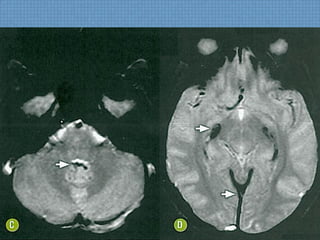

ACHADOS DE IMAGEM

• Hipossinal em T1 e hiperssinal em T2/FLAIR na

porção medial dos tálamos, região periaquedutal e

corpos mamilares;

• Restrição à difusão nos tálamos;

• Impregnação por Gadolíneo em corpos mamilares

pode refletir desmielinização aguda.

Reversível com reposição de B1!

EM NÃO ETILISTAS...

• Hiperssinal T2/FLAIR em núcleos bulbares de nervos

hipoglossos;

• Hiperssinal T2/FLAIR em núcleos pontinos dorsais de

abducente e facial;

• Acometimento difuso e multifocal do córtex cerebral,

principalmente em LF;

• KORSAKOFF  ATROFIA DOS CORPOS

MAMILARES!

ACHADO DE MAIOR SENSIBILIDADE: HIPERSSINAL

T2/FLAIR DOS CORPOS MAMILARES!